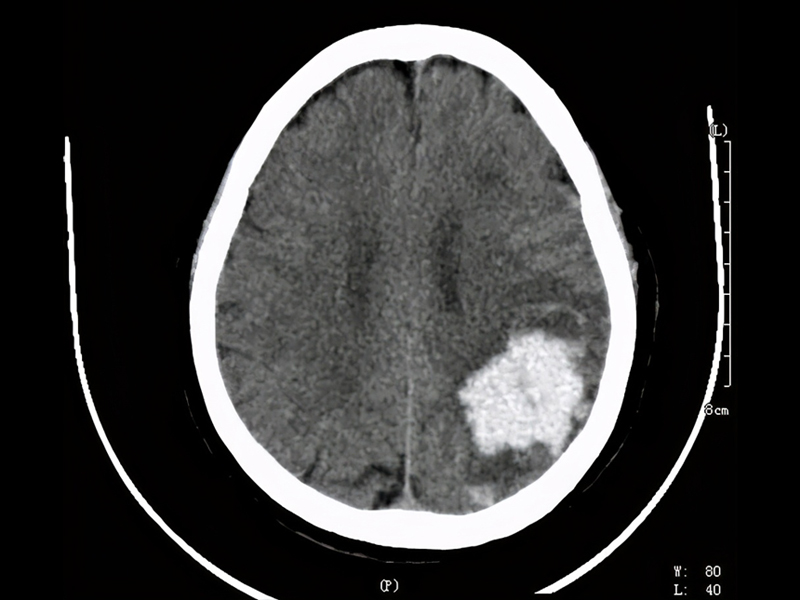

| 許多人都有午睡的習慣,短暫的午睡能快速恢復精力,提升工作效率。然而,研究顯示,若午睡時間過長,可能帶來更多的疲憊感,甚至對身體健康造成長期的負面影響,包括增加罹患心血管疾病、阿茨海默症及死亡的風險。 過去的研究多數集中在午睡的益處,例如對大腦健康的改善、認知能力的提升等。然而,這些研究往往忽略了午睡時間的長短對健康的影響,導致結論有一定的局限性。儘管「午睡時間對健康的影響」以及「最佳午睡時間」的議題仍有爭議,但多數研究結果建議:將午睡時間控制在 30 分鐘以內,有助於增強午睡的益處,同時減少午睡過久可能帶來的負面影響。 根據 2022 年哈佛醫學院參與的一項研究,老年人若午睡時間過長或頻率過高,罹患阿茲海默症的風險也會增加。研究指出,隨著阿茲海默症病情的加重,患者的午睡時間往往會變得更長、更頻繁。這表明午睡過長與阿茲海默症之間可能存在雙向關係,形成一種「惡性循環」。這些研究發現,阿茲海默症的發生與大腦中兩種特定蛋白質的積累有關,而午睡時間和頻率的增加,可能是這種蛋白質積累導致的症狀之一。 近年來,越來越多的研究關注到午睡時間的長短對心血管疾病的影響。多數研究將 30 分鐘作為午睡是否過長的標準線,發現短暫的午睡能夠有效消除疲勞、改善記憶力,增強反應速度,並對大腦及心血管健康帶來正面影響。 然而,究竟什麼時間午睡最好?午睡的最佳時間應該是多少才能有效減輕困倦感?專家建議,午睡時間最好控制在 30 分鐘內,以獲得最佳的健康效果。 |